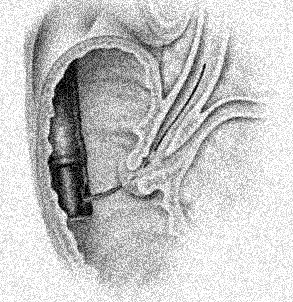

La

cholangio-pancreatographie retrograde par voie endoscopique

(ERCP): Methode invasive pour explore et

traitement de quelquesERCP affections de voie biliaire

: L'endoscopie est en place dans le tube digestif duodenum

D2 par la bouche et insertion un catheter en Teflon

avec guide (0.035) dans ampoule de Vater et guidee a canal

choledoque . Par cette voie on peu opacifie des voies

biliaires par contrast iodique ou de dilatation une portion stenosant de

voie biliaire par le Stent . Technique doit etre

realise sous anesthesie generale . Complication de cette

technique est : Pancreatite( 5% ) , hemorragie , perforation

et pneumoperitoine ou pneumoretroperitoine , ou infection de

voie biliaire ( cholangitis ) . Contre indication de cette

technique sont : deformation anatomie post -chirugical

, anormalie de l' oesophage , , estoma et duodenum , maladie

de coagulation du sang et sur le maladie a etat

instable

Par voie endoscopie duodenal

on peu place une chatheter a guide a spinter Oddie

au canal cholodioque . Radioopaque iodique peu

injecte et control sous scopie ( amplificateur de

brillance ) . Cliche expose |